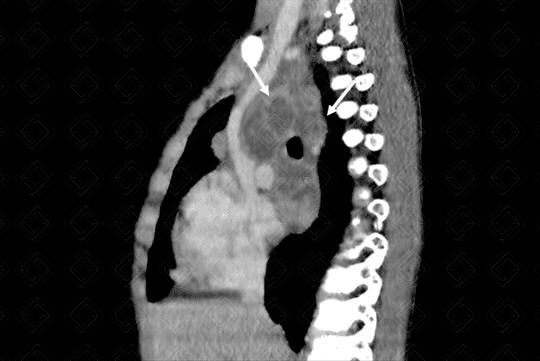

Texto alternativo para a imagem Figura 2. Créditos: Dra Elazir Mota - Rio de Janeiro/RJ

Estudo foi complementado com tomografia computadorizada do tórax, após a administração do contraste venoso: cortes coronal (figura 2) e sagital (figura 3), evidenciando linfonodomegalias mediastinais com realce periférico pelo meio de contraste e conteúdo interno hipodenso, não captante do meio de contraste (setas brancas), devendo representar áreas de necrose. Este aspecto tomográfico das linfonodomegalias, com área central de necrose, é muito sugestivo de doença granulomatosa, especialmente tuberculose.